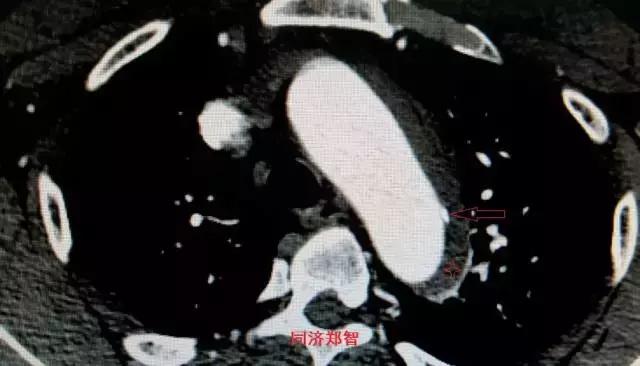

病例十一

平扫CT发现主动脉血管内孤立的钙化点(红色箭头所示),CTA证实为降主动脉溃疡合并壁间血肿。